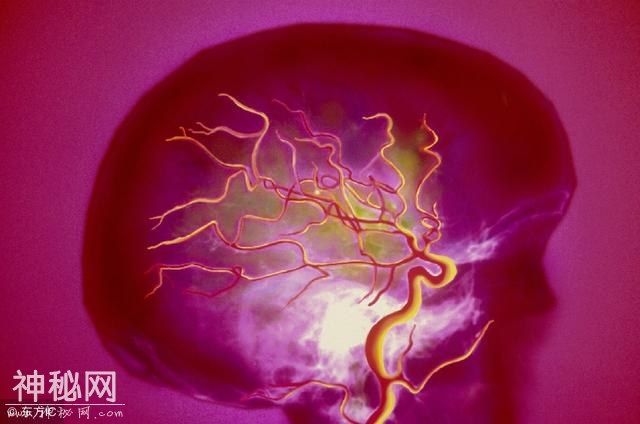

脑供血不足,指的是因血管堵塞等原因,导致人脑某一局部的血液供应不足而导致的脑功能障碍。脑缺血是导致神经类疾病的最常见因素,容易引发不可逆的脑部损害,如脑梗就是常见的因脑供血不足诱发的脑部疾病。

脑供血不足、有脑梗的5个暗示,早知道可救命!